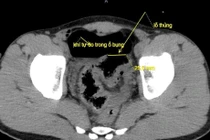

Tại đây, qua kết quả chẩn đoán hình ảnh các bác sĩ phát hiện dị vật hình dạng giống tăm tre đã xuyên thủng thành đại tràng, gây viêm phúc mạc khu trú.

Dị vật là tăm tre trong bụng bệnh nhân/ Ảnh SKĐS